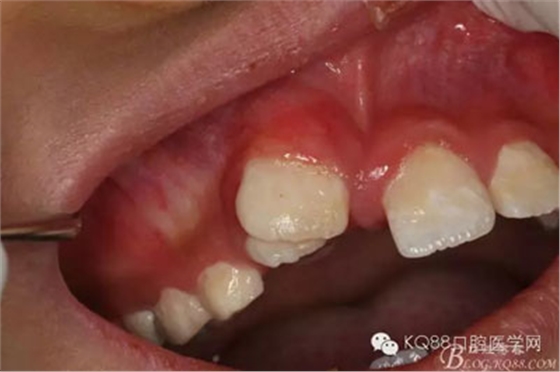

圖1.術(shù)前的患者口內(nèi)照片:11與12完全唇腭向重疊,11與21之間有3mm間隙